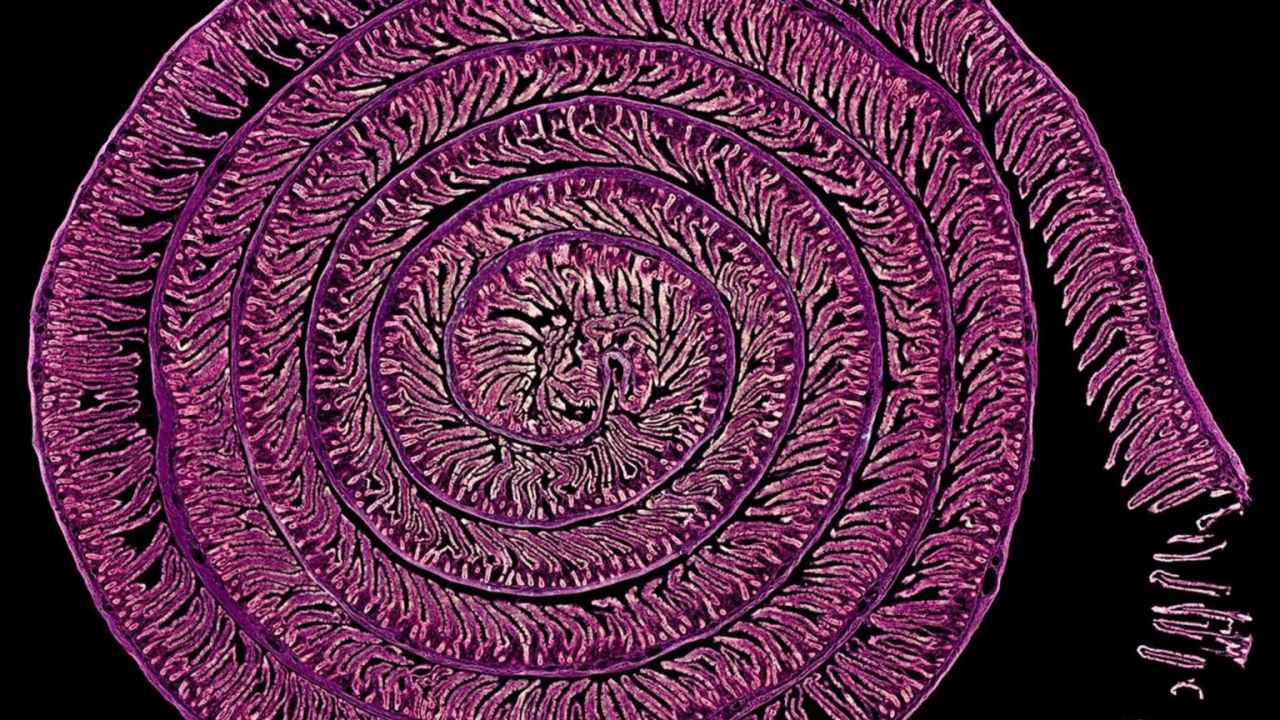

La fotografía científica 'Uzumaki' -espiral en japonés-, realizada por los científicos Daniel García Ovejero y Javier Mazarío Torrijos, del laboratorio de Neuroinflamación y del Servicio de Microscopía y Análisis de Imagen del Hospital Nacional de Parapléjicos, respectivamente, ha sido galardonada con el segundo premio en la modalidad Micro de Fotciencia21.

Una solución técnica para un órgano "difícil" de mirar por dentro La imagen seleccionada corresponde a una micrografía obtenida a partir de un corte de pocas micras de grosor que abarca 8,5 centímetros de intestino de rata, captada con un objetivo 10x, en la que se distinguen vellosidades y criptas intestinales dispuestas en una voluta o espiral.

El intestino es un órgano complejo de analizar al microscopio por su forma tubular y su gran longitud. Para abordar este reto, en histología se emplea la disposición de la muestra en "rollo suizo", que consiste en enrollar cuidadosamente el tejido intestinal antes de realizar los cortes finos, generando preparaciones en las que el órgano aparece organizado en espiral.